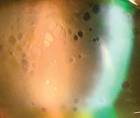

The patient’s entering VA was 20/40 OU with his habitual spectacle prescription. His pupils were equal, round, and reactive to light, without afferent pupil defect, and the extraocular motilities were full range of motion OU. The confrontation visual fields were tightly constricted 360° OU. Goldmann visual field testing was able to quantify a visual field constriction of approximately 5˚ OU (Figure 1). Refraction yielded a low myopic prescription that led to minimal improvement in visual acuity OU. The patient’s external ocular examination was unremarkable OU. His IOP was 15 mm Hg OD and 18 mm Hg OS with rebound tonometry. A dilated retinal examination revealed extensive peripheral bone spicules and macular pigmentation OU consistent with an RP diagnosis (Figure 2). Fundus autofluorescence highlighted the retinal pigmentary changes consistent with RP (Figure 3), and OCT scans confirmed atrophy of the macula OU without evidence of cystoid macular edema (CME) OU (Figure 4).